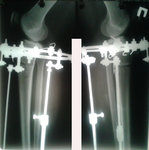

Дата операции 27.09.2016г

Дата снятия аппаратов 15.12.2016г.

Срок лечения 73 дня.